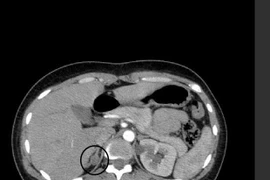

Bệnh nhân 36 tuổi bị co quắp tay chân vào viện khám phát hiện u vỏ tuyến thượng thận phải và u nang buồng trứng. Chỉ một lần phẫu thuật nội soi các bác sĩ đã giải quyết cả 2 loại u cho bệnh nhân.